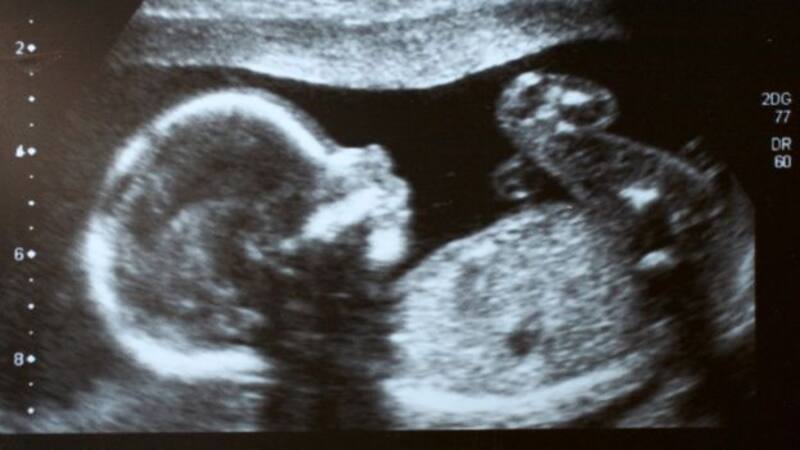

2. Distinto a otros virus: el Coronavirus daña y destruye la placenta, no al feto

Cuando las mujeres embarazadas se contagian con el virus Zika o el de la rubéola, estos virus pueden atacar directamente al feto porque traspasan la placenta. Pero con el virus Sars-CoV-2, la situación es distinta.

El virus puede atacar y destruir la placenta directamente, lo que provoca la asfixia y muerte del feto. Según un estudio publicado en la revista Archives of Pathology & Laboratory Medicine.

El docto David Schwartz, patólogo perinatal en Atlanta (Estados Unidos) y quien lideró el estudio dijo que nunca antes habíamos visto este nivel de destrucción por una enfermedad infecciosa. “Hizo que la placenta no fuera apta para llevar a cabo sus funciones. Estos fetos y recién nacidos murieron por asfixia por falta de oxígeno”, agregó.

En el estudio, Schwartz y su equipo examinaron 68 muertes perinatales en 12 países. Los 68 bebés nacieron muertos o murieron dentro de los siete días posteriores al nacimiento. Todos tenían madres que no estaban vacunadas y se habían infectado con el coronavirus durante el embarazo. Su estudio incluyó exámenes de las 68 placentas, así como 30 autopsias.

El cuadro, denominado placentitis por Sars-CoV-2, se produce por una acumulación de una proteína llamada fibrina, que provoca la coagulación en el sistema vascular del órgano; la muerte de células en la capa celular protectora de la placenta; e inflamación inusual en la placenta.

Entre las placentas analizadas, más de las tres cuartas partes del órgano estaban tan dañadas que el órgano no podía suministrar oxígeno y nutrientes al bebé en crecimiento. En otros casos, casi toda la placenta estaba muerta.